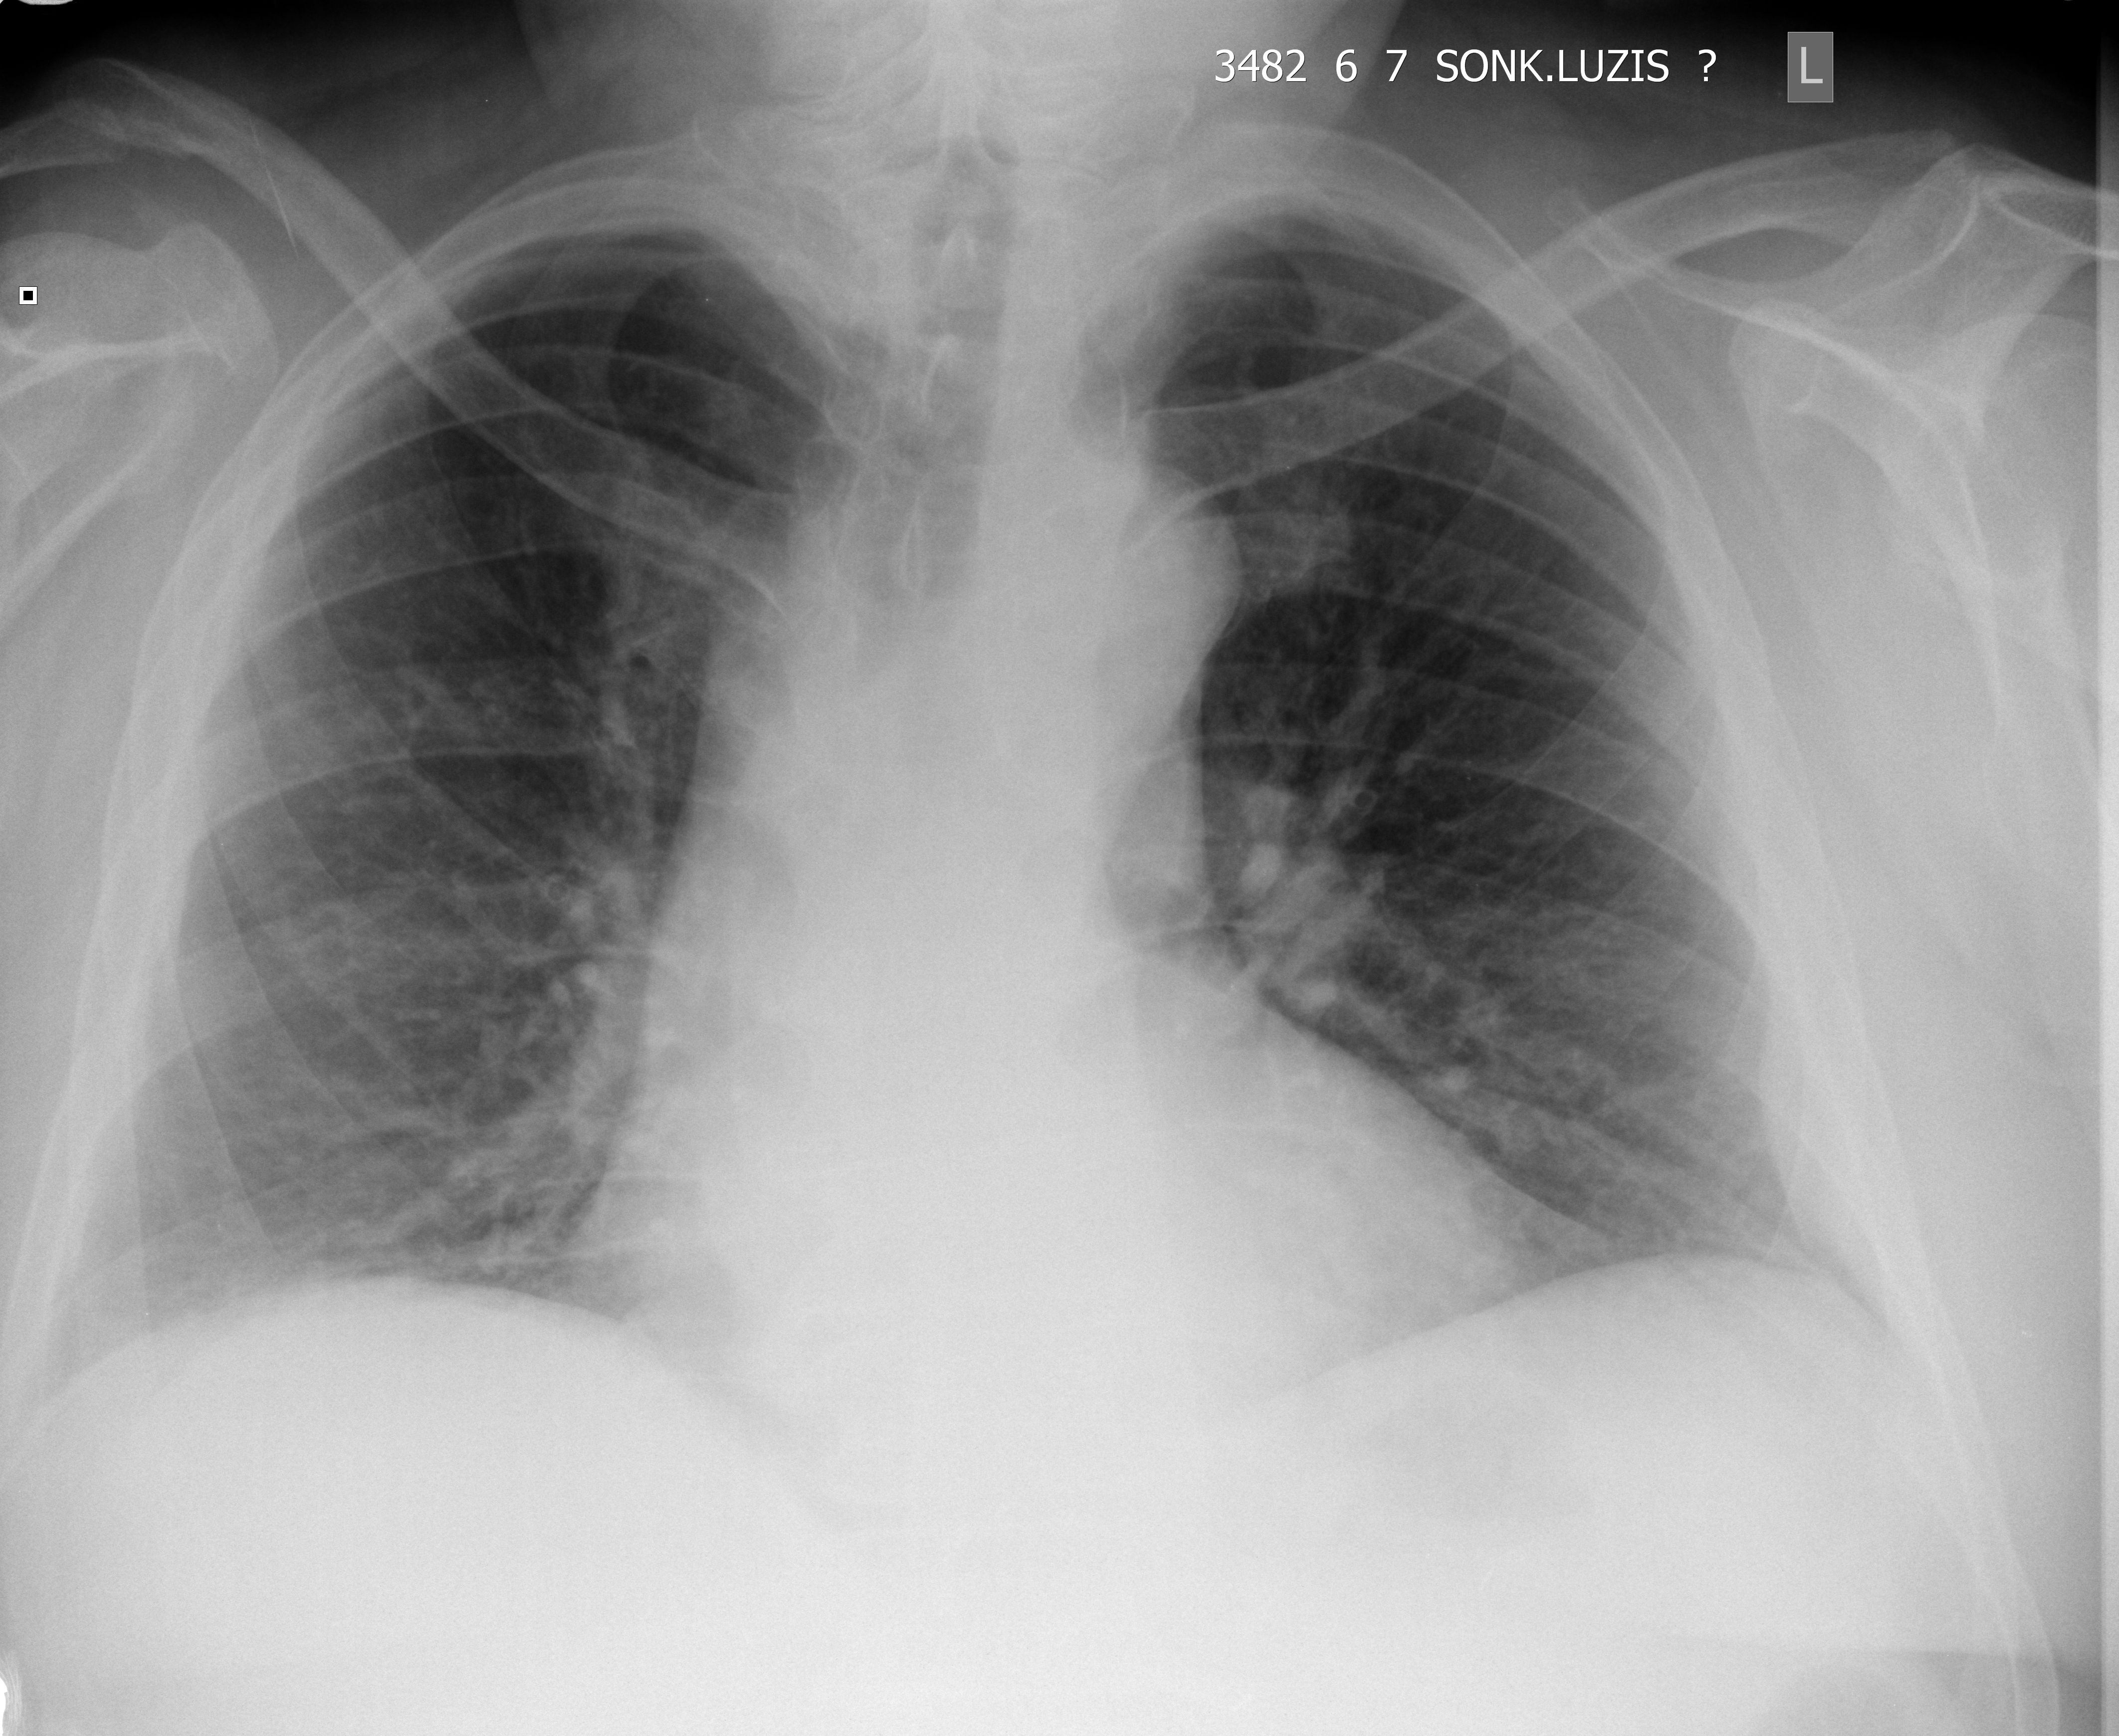

Мужчина, 59 лет, перелом ребра, травма месяц назад. Формирование костной мозоли.

Рентген - ответ отрицательный.